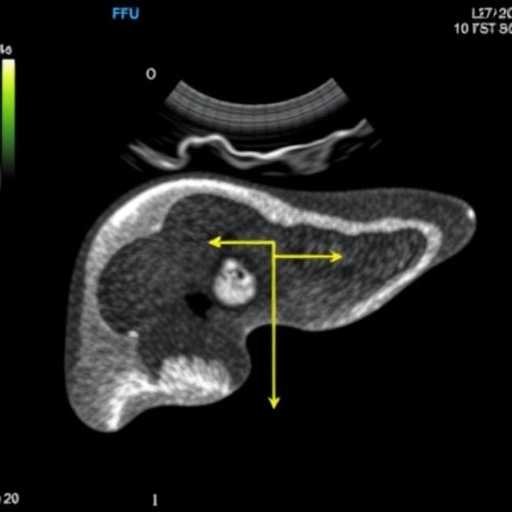

Historically, liver biopsy has been the benchmark for grading hepatic steatosis due to its direct histological evaluation. However, the invasive nature of biopsies, coupled with their inherent risks, high costs, and susceptibility to sampling errors, has underscored the urgent need for noninvasive diagnostic alternatives. Advanced imaging technologies such as magnetic resonance imaging-derived proton density fat fraction (MRI-PDFF) and proton magnetic resonance spectroscopy (^1H-MRS) have emerged as highly accurate, noninvasive modalities, yet their expense and limited accessibility restrict widespread clinical use. Recognizing these limitations, clinical researchers have turned to ultrasound-derived fat fraction (UDFF) as a promising, objective, and reproducible imaging technique that marries accessibility with precision in hepatic fat quantification.

A pioneering expert consensus led by Dr. Huixiong Xu and Dr. Hong Ding at Fudan University, China, responds to this clinical necessity by rigorously evaluating UDFF’s reliability, performance, and practical applicability. Published in the esteemed journal Portal Hypertension & Cirrhosis in March 2026, this comprehensive review synthesizes extensive multicenter trial data, cross-references with histopathological and MRI-based gold standards, and integrates expert clinical experience to provide a robust foundation for the systematic use of UDFF in routine practice.

The consensus study meticulously analyzed data from the largest multicenter cohorts to date, where UDFF measurements demonstrated strong validation against histopathology, MRI-PDFF, and ^1H-MRS. In parallel, the research benchmarked UDFF against established ultrasound grading systems, controlled attenuation parameter (CAP), and biochemical prediction models such as the fatty liver index and hepatic steatosis index. This multi-dimensional evaluation incorporated rigorous statistical assessments including correlation coefficients, intraclass correlation coefficients (ICCs), receiver operating characteristic (ROC) curve analysis, and Bland–Altman plots, all underscoring UDFF’s robust diagnostic capability.